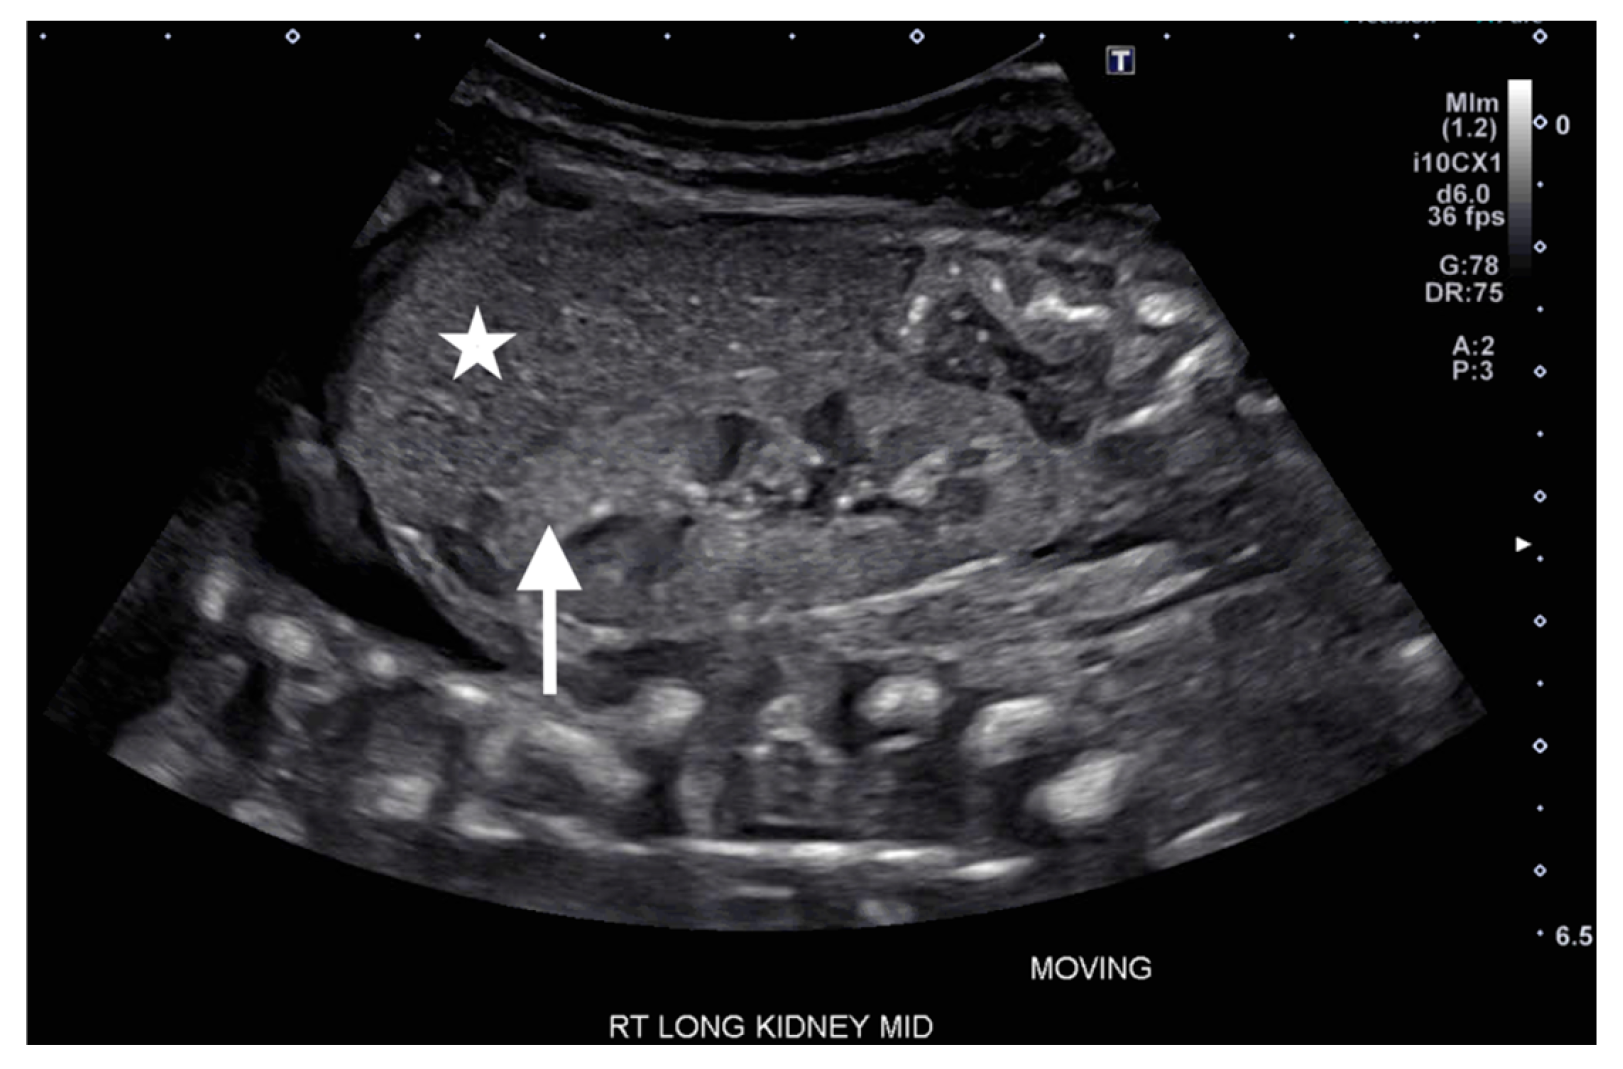

On DOL 5, the patient developed worsening abdominal distention with increased free fluid, rising lactate level, and continued oliguria with minimal brown-colored output, indicating potential bladder rupture. Renal ultrasound at that time demonstrated structurally normal kidneys and ureters, with contusive injuries in the parenchyma (Figure 1 and Figure 2). Pediatric urology was consulted. Diagnostic paracenteses and non-voiding cystogram showed no urinary leak. Computed tomography (CT) of the abdomen and pelvis was performed to further evaluate for free fluid or perforated viscus showed no renal contusion, but noted both kidneys had patchy opacification in the capsule and medulla, consistent with bilateral renal cortical necrosis (Figure 3). Cranial ultrasound was also performed at this time and showed focal parenchymal hemorrhage in the posterior portion of the left frontal lobe (Figure 4).

Figure 4.

Sagittal (left) and coronal (right) views of cranial ultrasound from day of life 5 showing focal echogenicity on the left side of the posterior frontal lobe white matter (arrows) with no intraventricular hemorrhage or ventriculomegaly.